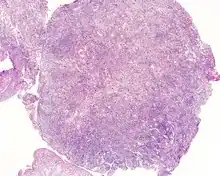

| An intermediate magnification of a H&E stained biopsy from an otic polyp. | |

By microscopic exam, the polypoid appearance is maintained, showing a granulation-type tissue reaction with edematous stroma and a rich investment by capillaries. The surface of the polyp is covered by stratified squamous epithelium with a prominent granular cell layer. The tissue is filled with lymphocytes, plasma cells, mast cells, histiocytes, and eosinophils. It is not uncommon to see plasma cells with Russell bodies and Mott cell formation. Depending on length of symptoms, multinucleated giant cells and calcifications may be seen. Other disorders may be concurrently present, especially since this is a post infectious/inflammatory disorder, and these include a cholesterol granuloma, "tunnel clusters" (glandular epithelial inclusions below the surface epithelium), and cholesteatoma.[3][4][5]